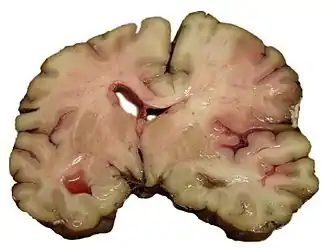

Срез мозга человека, умершего от инсульта